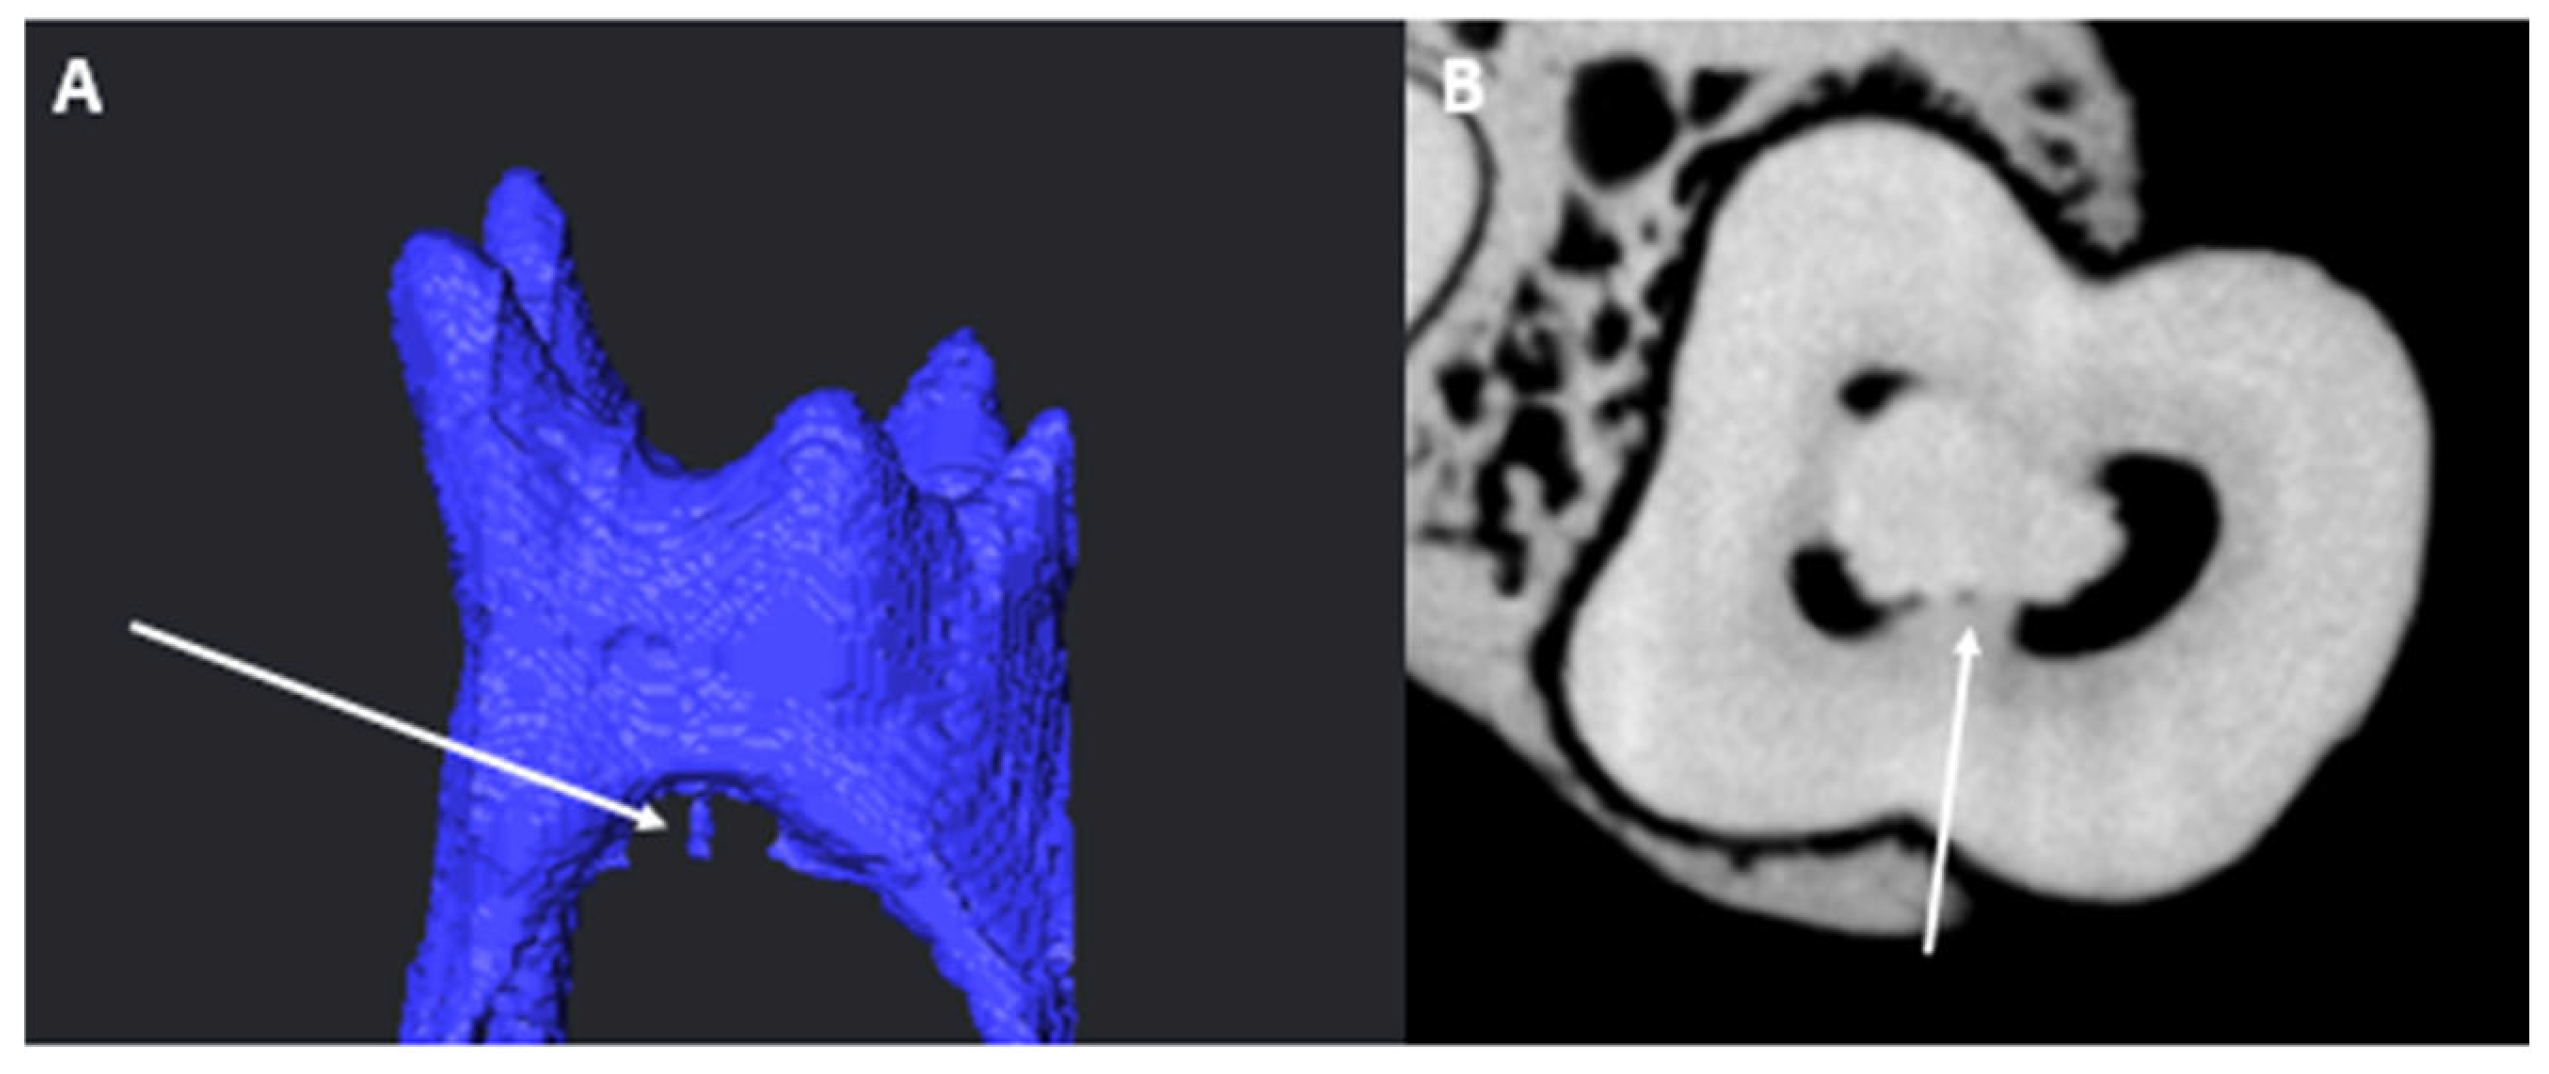

3.3. Number of Canals per Root

3.4. Chamber Canals

3.5. Accessory Canals (ACs)

3.5.1. M Root

3.5.2. D Root